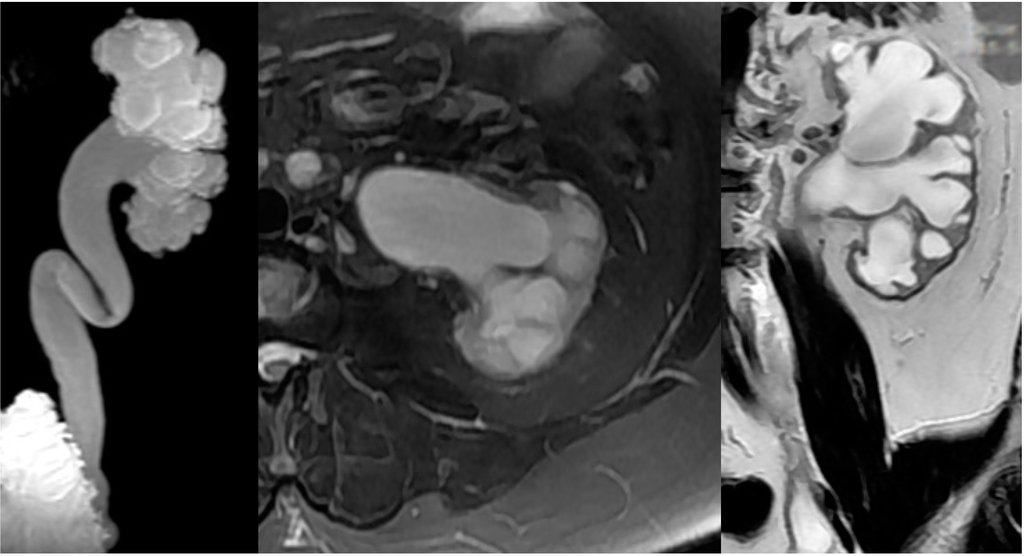

2.4. Upper Urinary Tract Imaging

2.4.1. Upper Urinary Tract Dilation (UUTD)

- Liao, L.M.; Zhang, F.; Chen, G. New grading system for upper urinary tract dilation using magnetic resonance urography in patients with neurogenic bladder. BMC Urol. 2014, 14, 38–45. [Google Scholar] [CrossRef] [PubMed]